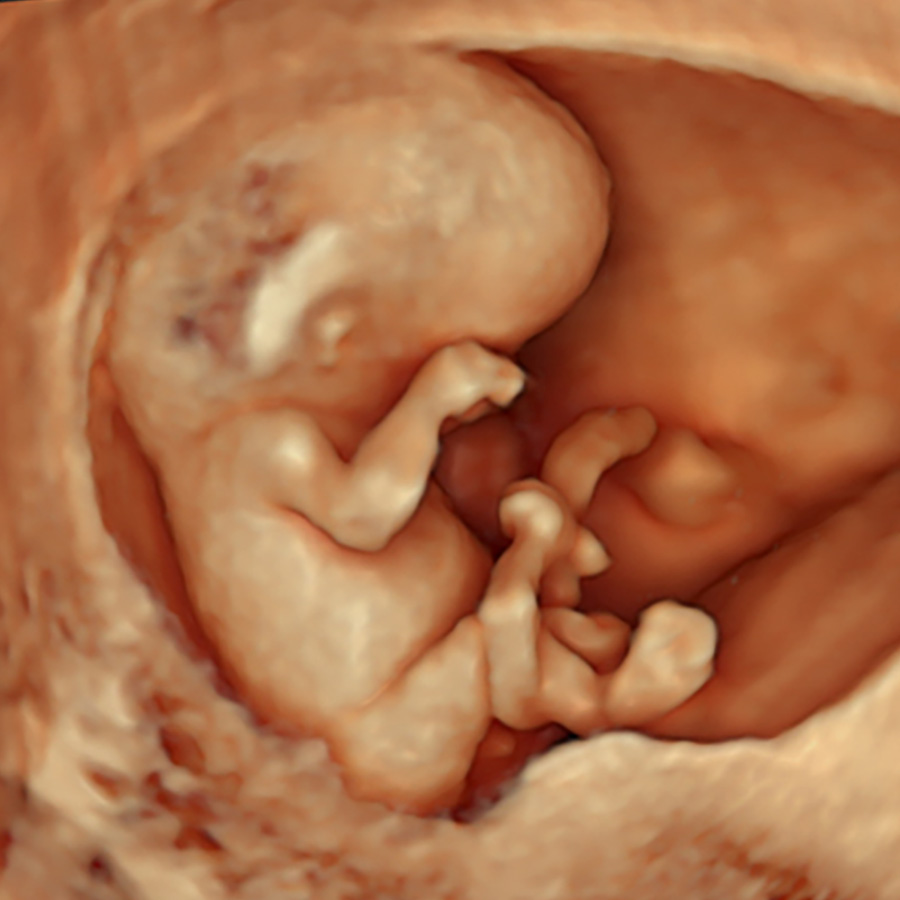

Combining the earliest structural screening for most severe anomalies with precise NT measurement in a single scan

At this early stage the baby is very small, so the scan is usually done through the vagina (transvaginal) to get the sharpest images. The transvaginal probe sits closer and uses higher-frequency sound, giving better resolution for tiny structures including the NT.

We can scan through the tummy (transabdominal) if the view is good, but detail is often lower because the beam travels further and is partly absorbed by the abdominal wall; we’ll use whichever gives the best view—both are safe.

We scan first to confirm NIPT is appropriate. Several early major anomalies like acrania, amniotic band syndrome, body-stalk anomaly, cloacal exstrophy, limb–body–wall complex, pentalogy of Cantrell, and sirenomelia, are usually non-genetic with a very poor prognosis.